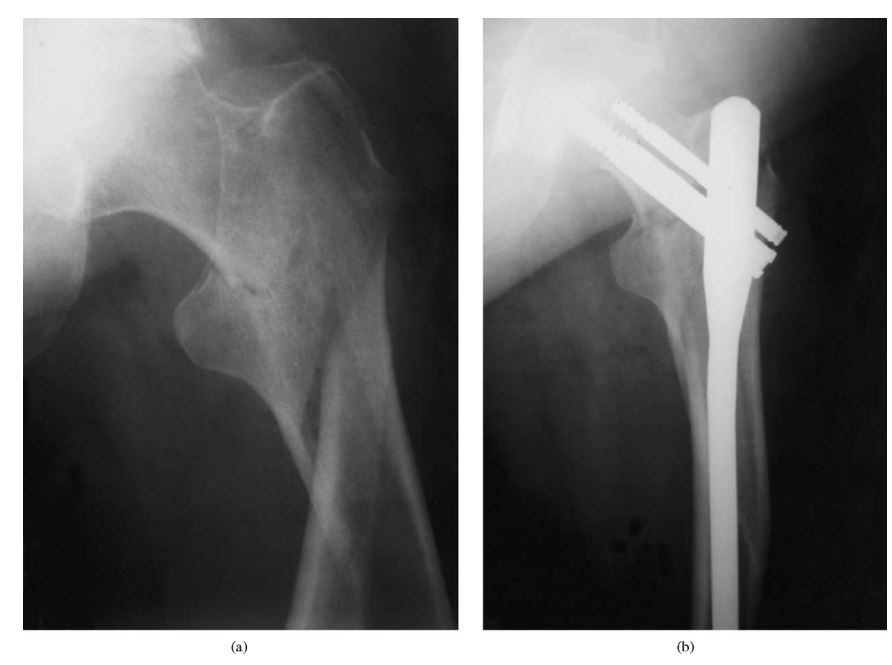

22

Q

Pathological fracture: Metastases

56 year old, history of fall in bathroom, unable to ambulate thereafter.

1. Describe the imaging findings.

2. What is your diagnosis?

3. How will you approach such a case?

4. What investigations will you perform to ascertain your diagnosis

5. What will be your management for this patient?

This is the AP and lateral projection of the index patient’s left hip, showing a spiral/long oblique subtrochanteric femur fracture with mottled appearance proximal and distal to the fracture line.

1. What is your diagnosis?

This is most likely a pathological fracture of the left subtrochanteric femur.

1. How will you approach such a case?

ATLS

Secondary survey - Ensure no other areas of injuries such as head, spine, other limbs.

Take history and examination from patient

History - current or previous Hx of cancer or infection, any lumbs or bumps, any other symptoms indicating primary malignancy (haematuria, haematochezia, dark coloured stools, per vaginal bleeing, haemoptysis, altered bowel habits), constitutional symptoms (LOA, LOW).

1. What investigations will you perform to ascertain your diagnosis.

Xray:

Full length view of the left LL with hip and knee joint in view.

If also complaining of pain at right LL, the same views required.

Blood Ix: FBC, LFT, electrolytes like calcium, ALP, tumour markers for breast, endocrine, ovarian, bowel Cas, electrophoresis ofr M band.

Imaging Ix: CT TAP for primary and metastases.

1. What will be your management for this patient?

Multidisciplinary team approach, in which will involve

• clinical oncologist

• physiotherapist

if lung mets present - respiratory physicians/ thoracic surgeons.

to discuss

• if primary tumour is operable

• prognosis of patient

• curative vs palliative intent , what options suitable,

Orthopaedic management

Aim for operative intervention to reduce and stabilise fracture because

a) Regain patient’s mobility - to reduce risk of DVT/PE, sacral sore, pneumonia.

b) Improve fracture healing - pathological fracture has prolonged/non-healing, added by the fact it is subtroch region with precarious blood supply.

c) Ease nursing care - once fracture fragments are stabilised as one unit, reduced pain, ease turning of patient.

Aim during operation is to get

A) Lenght, Allignment, Rotation with a Stable fixation.

Choice of fixation is cephalomedullary nailing spanning the whole femur.

If contralateral femur also has mottled appearance with no fracture, will score Mirel, consider prophylactic cephalomedullary nailing spanning the whole femur as well.

https://sci-hub.se/https://doi.org/10.1016/S0020-1383(03)00101-3

If primary tumour is breast or prostate (male) with better prognosis for patient, will consider an endoprosthesis replacement with a long stem.

• rate of reoperation is lower at 2 years compared to osteosynthesis.

B) Bone biopsy for HPE

• after consultation with tumour service.